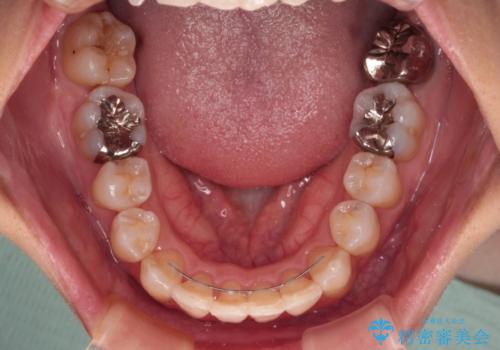

上顎前歯の歯軸が顕著に改善され、非常に口の閉じやすい歯列に仕上げることができました。

上下の咬み合わせは上顎歯列全体が歯1本分前にずれている状態であり、さらに上顎歯列はV字型に尖っていたため、上下前歯は全く接触していない状態でした。